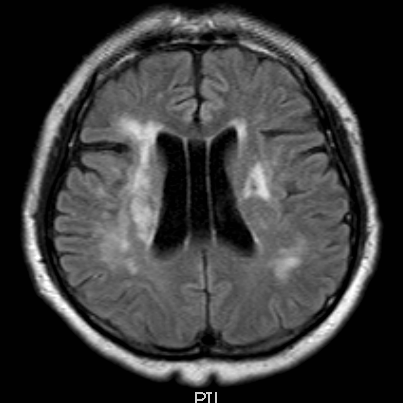

T2

右侧MCA长节段血管变细狭长

长节段MCA血管狭长变细,尤以近端为重